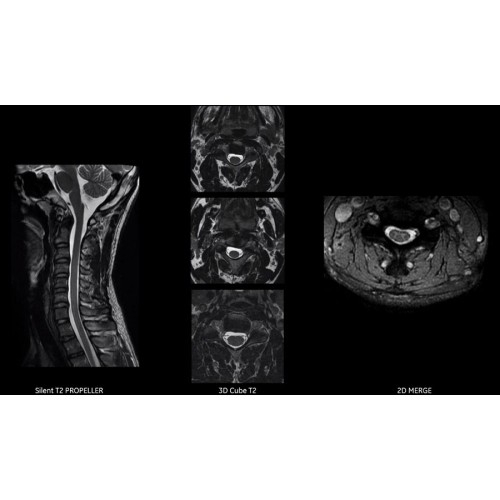

Детализация изображений

Система SIGNA Pioneer воплощает поразительные достижения в области визуализации. Передовая технология Total Digital Imaging (TDI) позволяет добиться большей четкости изображений и на четверть повысить соотношение сигнал/шум.

TDI построена на трех базовых компонентах:

• Технология Direct Digital Interface (DDI) использует независимый аналого-цифровой преобразователь для оцифровки сигнала от каждого из 97 радиочастотных каналов, что обеспечивает значительное увеличение качества за счет уменьшения фонового шума.

• Технология Digital Micro Switching (DMS) — это следующее поколение технологий радиочастотных катушек, основанное на замене аналоговых схем блокировки сверхбыстрыми микропереключателями (MEMS), что делает возможным быстрое переключение катушек для дальнейшего расширения возможностей визуализации с нулевым TE.

• Технология Digital Surround Technology (DST) — это новая технология объемной оцифровки данных, объединяющая сигналы от каждого элемента катушки. Прекрасное соотношение сигнал/шум и чувствительность поверхностных катушек в сочетании с превосходной однородностью и высокой проникающей способностью встроенной радиочастотной катушки — все это позволяет создавать качественные изображения не только позвоночника, но и всего тела.

Благодаря революционному программному пакету Silent Suite уровень шума снижается до 77 дБ, что всего на 3 дБ выше уровня окружающей среды. Программный пакет Silent Suite теперь включает полный пакет приложений для исследования ЦНС (T1, T2 FLAIR, DWI10, МРА). Кроме того, мы расширили возможности визуализации Silent за пределы ЦНС для исследований скелетно-мышечной системы и позвоночника. Silent Suite – платформа, содержащая в себе все импульсные последовательности для бесшумного сканирования.